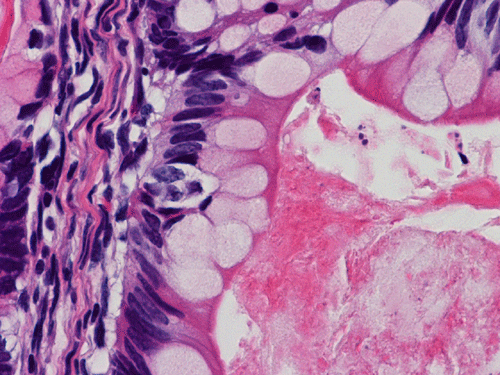

The entire specimen was submitted for histologic examination. The bulk (over 99%) of the tumor was composed predominantly of mature intestinal elements (Panel A, B, and C) and skin, respiratory type mucosa, cartilage, and small amount of mature neural parenchymal tissue of the central nervous system (Panel D and E). Neither immature nor malignant elements are present. Small microscopic foci of well demarcated, neural parenchymal tissue with increased atypia (arrow in panel F) are noted. On higher magnification (Panel G and H), these areas contain large, bizarre appearing cells with dark chromatin but no prominent nucleoli. There are also scant multinucleated cells and mineralized substances (arrow in Panel H). Another example of these foci is illustrated in Panel I, J, and K. These atypical foci comprised less than 1% of the volume of the tumor. They are all microscopic in size and show no evidence of expansion or invasion into the surrounding tissue.

While AFP is typically produced by yolk sac tumor component, it has also been demonstrated in mature teratoma components non-yolk sac tumor component including teratoma component  11, 12, 13, 14. Expression of AFP has been demonstrated in the columnar epithelial components. Teratomas, as in our case, are not typically associated with elevated AFP although two rare cases have been documented previously 15, 16. The elevated AFP probably originates from the columnar epithelial components that express AFP.